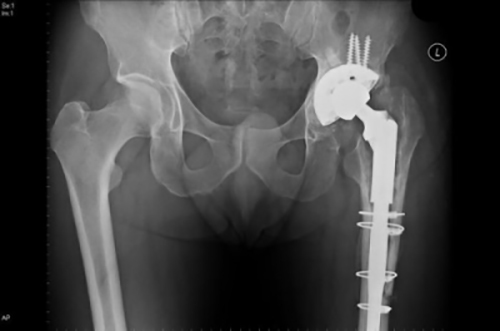

Հիշեցնենք, որ ՄՌՏ-ի համար գոյություն ունեն հակացուցումներ: Մասնավորապես, մարմնում մետաղական իմպլանտների առկայությունը համարվում է դրանցից մեկը: Սակայն հարց է ծագում, կարելի՞ է, արդյոք, այդպիսի հետազոտություն իրականացնել, եթե առկա են ատամների մետաղական պսակներ, ատամնային իմպլանտներ, թիթեղներ և մարմնում շտիֆտներ:

Ընդհանուր օրենքը հետևյալն է. ամեն ինչ կախված է այն նյութից, ինչից պատրաստված են շտիֆտները, իմպլանտները և պսակները: Եթե խոսքը ժամանակակից մետաղակերամիկայի մասին է, ապա անհանգստանալու բան չկա, ՄՌՏ կարելի է իրականացնել:

ՄՌՏ կարելի է իրականացնել նաև այն դեպքում, երբ հիվանդի մոտ տեղադրված է տիտանե թիթեղ. այն կենսաբանական առումով իներտ է և չի արձագանքում մագնիսական դաշտի ազդեցությանը: Իսկ ահա, տեղադրված պողպատե թիթեղի դեպքում բժիշկները խորհուրդ չեն տալիս ՄՌՏ իրականացնել, քանի որ այն կարող է տեղաշարժվել:

«ՄՌՏ ուղեգրված հիվանդները պետք է իմանան, թե ինչ նյութերից են իրենց մոտ տեղադրվել ատամնային կամ հոդային շտիֆտներ: Այդ մասին նրանց տեղեկացնում են տվյալ ծառայություններն իրականացնող բուժհաստատությունները: Եթե այդ շտիֆտները պատրաստված են պարամագնիսական նյութերից, ապա ամեն ինչ նորմալ է: Եթե հիվանդը չգիտի, թե ինչ նյութից են պատրաստված շտիֆտները, տոմոգրաֆով հետազոտությունից հետո, հետազոտման այն շրջանը, որտեղ գտնվում է կոնստրուկցիան, կարող է տաքացման հետևանքով բորբոքվել: Սակայն ՄՌՏ հետազոտության որակի վրա այն առանձնակի ազդեցություն չի ունենում»: